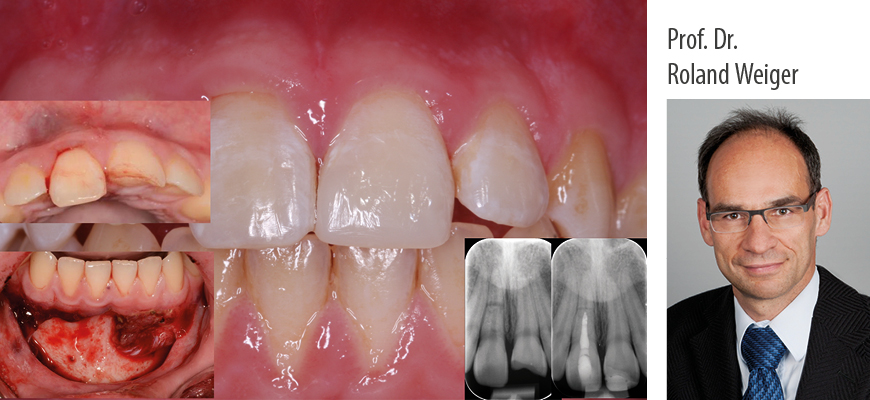

Online-Seminar: Prof. Dr. Roland Weiger: Das Zahntrauma - Was sollte der Zahnarzt wissen und tun? in 5 Modulen.

Das Zahntrauma kommt nicht nur bei jungen, sondern auch bei älteren Patienten immer häufiger vor. Mit abgesicherten Therapiekonzepten und einem strukturierten Vorgehen lassen sich sowohl einfachere als auch komplexere Situationen nach dentalem Trauma beherrschen. Das gilt für die Notfallbehandlung und die Nachsorge als Voraussetzung für den langfristigen Erhalt der zumeist betroffenen Frontzähne.

In fünf Modulen werden Ihnen zu den relevanten Formen des Zahntraumas (Zahnfrakturen u. Dislokationsverletzungen) das aktuelle Wissen, die Vorgehensweisen und praxisnahe klinische Tipps für die Umsetzung vermittelt.

Dies erfolgt anhand vieler klinischer Beispiele.

Kurzvita Prof. Dr. Roland Weiger, Universitäres Zentrum für Zahnmedizin Basel (UZB)

Prof. Dr. Roland Weiger erwarb das zahnmedizinische Staatsexamen 1985 an der Universität Tübingen. In der Abteilung für Zahnerhaltung promovierte er 1987 und qualifizierte sich wissenschaftlich. Bis 2002 arbeitete er dort, zuletzt als Professor für Endodontologie (C3). 2002 nahm er den Ruf auf den Lehrstuhl für Parodontologie, Endodontologie und Kariologie der Universität Basel (CH) an. Neben seiner Funktion als Klinikdirektor ist er Mitglied der Geschäftsleitung des seit 2016 bestehenden Universitären Zentrums für Zahnmedizin Basel UZB.

Seine Forschungstätigkeit befasst sich mit verschiedenen Teilgebieten der Zahnerhaltung insbesondere der Endodontologie. Der klinische Schwerpunkt und die Vortrags-/Fortbildungstätigkeit konzentrieren sich auf die Endodontologie und die dentale Traumatologie. Wissen und klinische Erfahrung manifestieren sich in zahlreichen Kursen, die er in den letzten 25 Jahren gehalten hat.